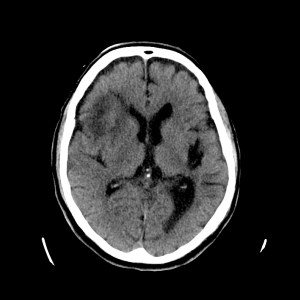

Esta imágen plantea dudas, puede ser una masa o un foco de sangrado, es más, si de esta segunda imagen asumimos que la zona de densidad aumentada corresponde a un sangrado, la pregunta a realizarse ahora es ¿de qué tipo? ¿Es un sangrado intraparenquimatoso, una transformación hemorrágica de un infarto o es otra cosa?

Pues bien, ante los hallazgos descritos, se clarifica que estamos ante un paciente el cual no tiene una masa y que ha sufrido una lesión isquémica hace diez días. Ahora, sobre dicha lesión, tenemos una imagen con un aumento de densidad que sugiere sangrado por una parte y otra hipodensidad en la perifería que correspondería a un edema. Por tanto, descartamos un sangrado intraparenquimatoso de novo. El paciente tiene más de 65 años, no es hipertenso, la imagen del sangrado no es de alta densidad, lo que se opone a una fase aguda o hiperaguda, y tenemos el TC de cráneo previo donde ya se advertía un proceso de tipo isquémico. Por tanto, nos quedan dos opciones, o estamos ante un resangrado de un ACV o estamos ante una Perfusión de lujo.